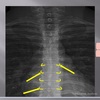

1

Q

LATERAL CERVICAL LANDMARKS lateral cervical view

6

Lateral cervical view

A

spinous process C2-C7

How well did you know this?